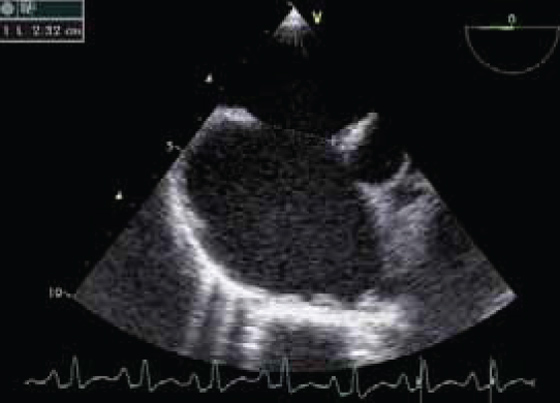

- Shunts gauche – droite dominant la scène.

- Communication interventriculaire (CIV) large.

- Persistance du canal artériel.

- Canal atrioventriculaire (chez le trisomique 21).

- Risque d’hypertension artérielle pulmonaire (HTAP) irréversible si le shunt est opéré trop tard. Chirurgie en général dans la première année de vie (figures 3 et 4).